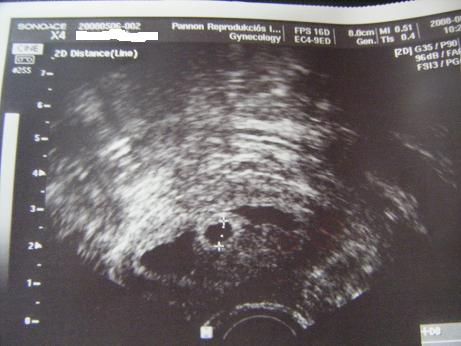

Gratulálok a szép kis petezsákodhoz! Én nem látok másikat, de nem is vagyok szakember. Valszeg ők nem maradtak meg, felszívódtak. Ha haematomád van, akkor még lehet vérezgetés, barnázgatás. Nekem is volt. Ha lesz, ne ijedj meg, de azért menj el dokihoz. A biztonság kedvéért. Oksi?! Pussz!!!